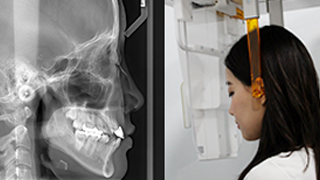

SMILE FACE DENTAL CLINIC’s 12-step orthodontic diagnostic system is an advanced process that systematically analyzes a patient’s teeth, jaw structure, facial balance, and bite, allowing us to establish the most optimal treatment plan.

03 Cephalometric (lateral skull) X-ray imaging

11 V-ceph

12 Analysis and Treatment Planning